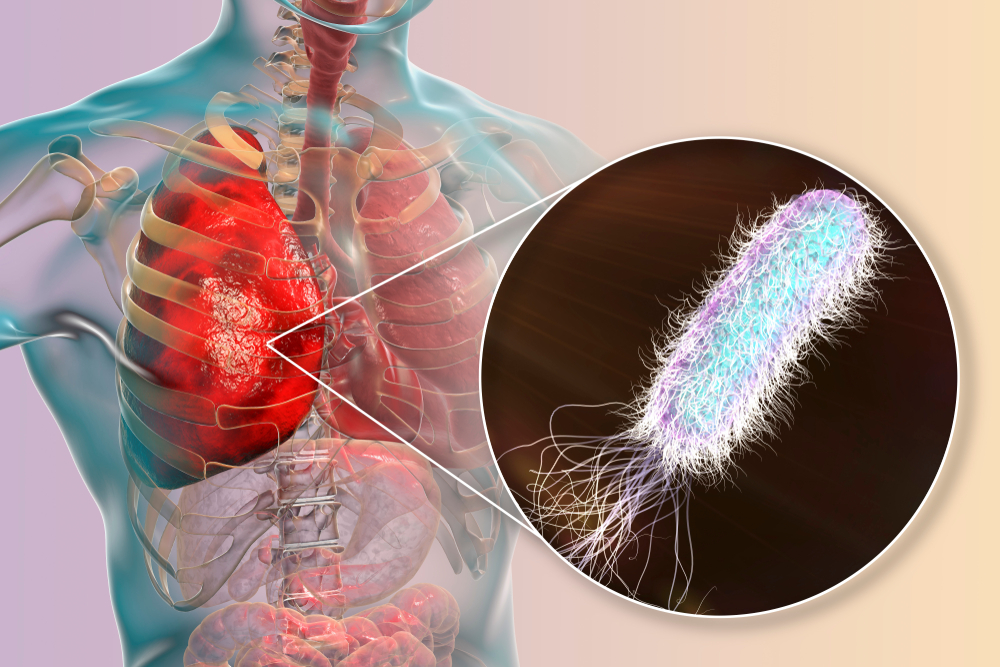

Фотографии бактерий, вызывающих бактериальные пневмонии у животных

Раздел: Другие животные